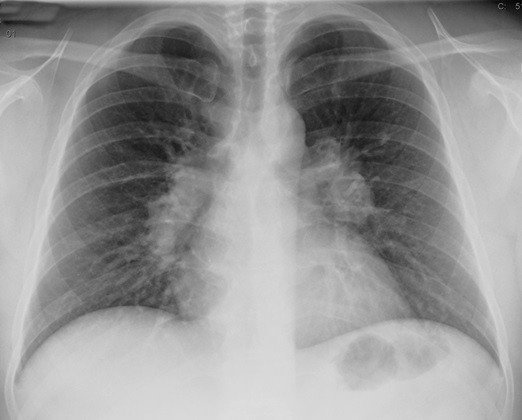

САРКОИДОЗ ЛЕГКИХ

Саркоидоз легких: степени

Саркоидоз легких — первая степень. Первая стадия саркоидоза характеризуется увеличением внутригрудных лимфатических узлов.

Саркоидоз легких — вторая степень. При второй степени саркоидоза наряду с этим определяются выраженные интерстициальные изменения и очаги различной величины преимущественно в средних и нижних отделах лёгких.

Саркоидоз легких — третья степень. В третьей степени саркоидоза выявляются значительный диффузный фиброз в лёгких и крупные, обычно сливные фокусы, а также выраженная эмфизема, нередко с буллёзно-дистрофическими и бронхоэктатическими полостями и плевральными уплотнениями.